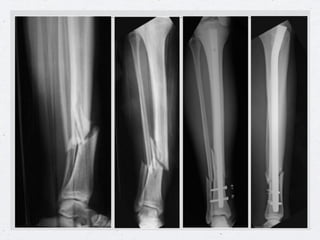

Enclavado de tibia en fractura cerrada

Clavo sin Bloqueo   Clavo con Bloqueo con aletas   Clavo con Bloqueo con Pernos

Clavo centromedular detibia • Tabla ortopédica • Tracción longitudinal • Tracción trans- calcánea o estribo • Rodilla flexionada Instalación para • Control radioscópico enclavado tibial. de la reducción

Instalación para enclavadode tibia • El canal endomedular se aborda por delante de la espina tibial • Introducción de la guía, del alisador y finalmente el clavo.

Enclavado de tibiaen fractura cerrada Clavo sin Bloqueo Clavo con Bloqueo con aletas Clavo con Bloqueo con Pernos